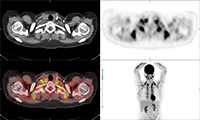

Thyroid imaging with pinhole collimator after the injection of free Tc-99m pertechnetate shows a rounded focal photopenic defect in the region of the left lower thyroid lobe caused by a nonfunctional photomultiplier tube. Focal intense activity seen in the right antecubital region and along the right lateral abdominal wall on Tc-99m MDP scan is related to extravasation of radiopharmaceutical at the injection site with scatter of photons from the forearm to the abdominal wall (narrow angle scatter). Fused axial FDG PET-CT (B), PET axial (C), CT axial (D) and MIP PET (E) images demonstrate intensely FDG avid lymph node in the right axilla. Infiltration of FDG at the injection site in right antecubital fossa results in lymphoscintigraphy with FDG migrating to the regional nodal basin via the lymphatic ducts.

Fused axial FDG PET-CT (B), PET axial (C), CT axial (D) and MIP PET (E) images, demonstrate intensely FDG avid lymph node in the right axilla. Infiltration of FDG at the injection site in right antecubital fossa results in lymphoscintigraphy with FDG migrating to the regional nodal basin via the lymphatic ducts. Technetium 99m MDP whole body bone scan shows photopenic defect on the midline pelvis from the attenuation of a belt buckle.

63 year-old woman with right femoral hardware for 3 years presented with right leg pain. Whole body Tc-99m HMPAO tagged WBC (A) scan demonstrated focal abnormal activity in the distal right femur which may represent infection or focal marrow. Tc99m sulphur colloid bone marrow scan (B) four weeks later demonstrates similar focal uptake in the distal right femur confirming the etiology as uptake in displaced marrow and not infection. 60 year-old man with history of lung cancer and left hip arthroplasty suffered from stiffness in the left hip region. Axial CT, FDG PET, fused axial, and coronal PET-CT demonstrates increased uptake of FDG in heterotopic ossification in the musculature of the left thigh. 30 year-old woman with history of lymphoma. Axial CT, PET, PET-CT fused, and PET MIP images demonstrate intense FDG activity in the bilateral neck and paravertebral regions with a symmetrical distribution. Cross-sectional images clearly show that activity in the neck corresponds to fat and therefore consistent with brown fat activity. Brown fat activity is seen more commonly in younger patients and is also increased in response to hypothermia (so keep patients warm both pre and post injection of FDG).